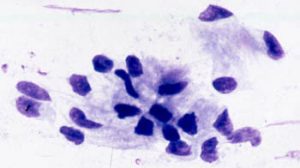

A microscope slide smear of some of the fluid and surface tissue harvested from the endometrial surface of the uterus is prepared and then stained using a differential hematology stain. The slide is evaluated for the presence or absence of inflammatory cells, specifically neutrophils.

Slide photos courtesy of Dr. Jonathan F Pycock, B.Vet.Med., Ph.D., D.E.S.M., M.R.C.V.S.